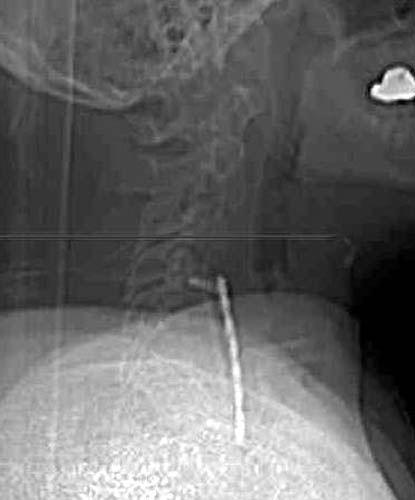

Scout image from a CT 3 month later suggests ventral displacement of the

bone graft and fixation plate. |

This axial CT taken at the same time shows to

better advantage how the distal screws are fully out of the ventral cortex of C7

on the right hand distal screw and only 1 thread of the left hand distal screw

remains in the bone itself. The fixation plate is also 1cm ventral to the body

of C7 at this level. |